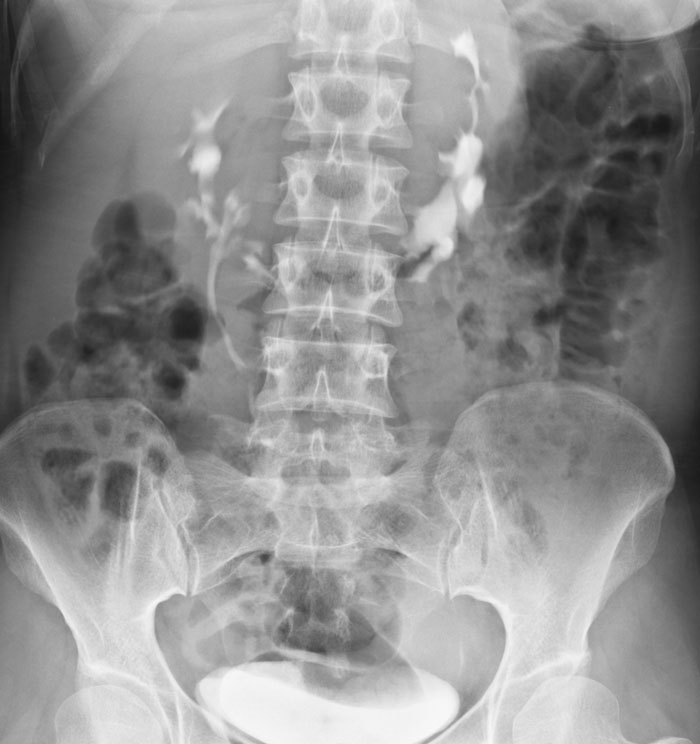

Asistí a una autopsia en la que el sujeto examinado tenía un riñón tan grande que se extendía a ambos lados del cuerpo en lugar de tener 2, uno a cada lado del cuerpo.

Riñón en forma de herradura. Se estaban haciendo varias autopsias a la vez y, cuando se descubrió, todos los médicos dejaron lo que estaban haciendo y se acercaron a mirar. Así que sospecho que las probabilidades son superiores a 1 entre 500.